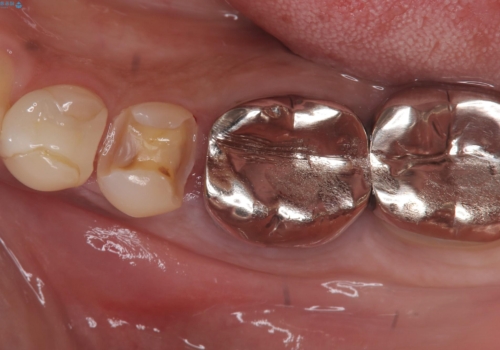

- 主訴:銀の詰め物が何本か入っているので白くしていきたい

保険適用のメタルインレーのやり替え希望だったため、審美性・適合性の良いセラミックインレーでのやり替えとなりました。

メタルインレーを除去したところ、二次カリエスうを確認したため除去・CR裏層の後、形成・印象しています。